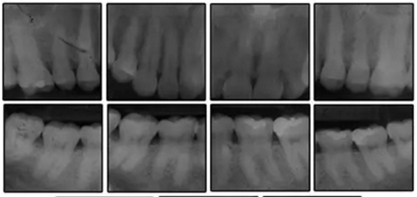

圖3. 治療前頭影側(cè)位片,頭影測量描跡圖和全口X光片

患者是一名39歲的白人婦女,病史不明。她主訴是她的右側(cè)顳下關(guān)節(jié)有不適癥狀,并希望改善她的笑容。她有一個對稱的臉型和一個II類2分類的微笑。她的側(cè)貌是凸的,90°的鼻唇角和骨性下頜骨發(fā)育不足??趦?nèi),上頜中線與面部重合,但下頜中線向右側(cè)偏移5mm;存在6mm的深覆蓋。她的兩側(cè)都是I類磨牙關(guān)系,左側(cè)是I類尖牙關(guān)系,右側(cè)是完全的II類尖牙關(guān)系。下頜右側(cè)第二前磨牙先天性缺失(圖1和圖2)。最初的全景片顯示了足夠的骨質(zhì)水平和全部的第三磨牙(圖3)。治療前的頭影測量片片和相應(yīng)的頭影測量圖(圖3)證實ANB為7°,Wits評估為6 mm的骨性II類錯合(表)。上頜切牙相對與面部和顱底的位置很好。下頜切牙前傾。診斷為II類2分類錯合畸形,伴有骨性下頜發(fā)育不足,右側(cè)顳下頜關(guān)節(jié)癥狀,下頜中線向右側(cè)偏移5mm,先天性右下第二前磨牙缺失。